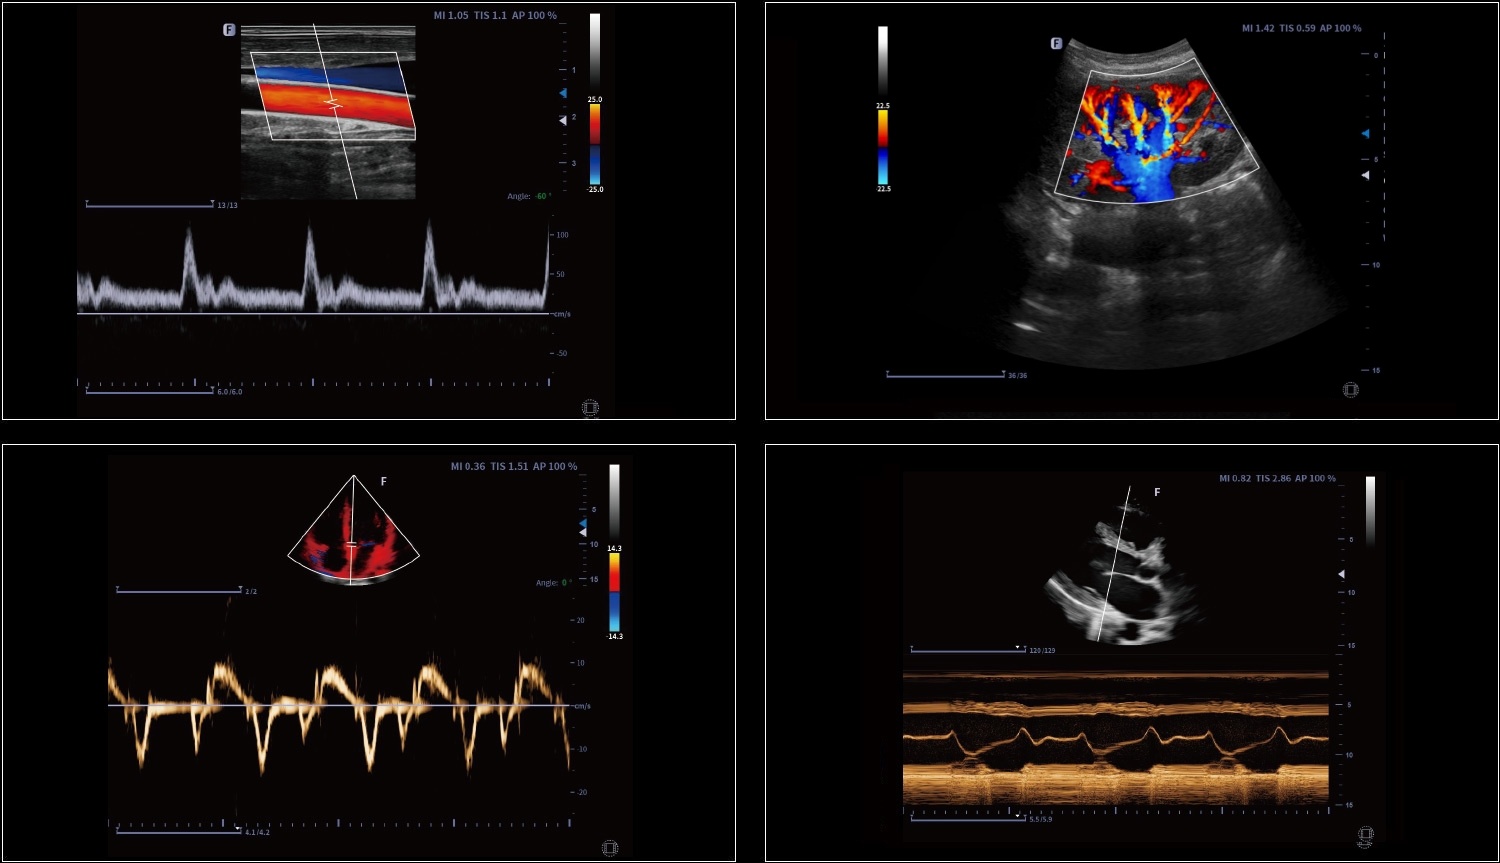

Technologia krzywoliniowego M-Mode (CAM) umożliwia wyświetlanie wszystkich przestrzennych i czasowych relacji ruchów segmentów mięśnia sercowego podczas cyklu sercowego w sektorze skanowania. Zapewnia to nową metodę pomiaru do ilościowej analizy zaburzeń ruchów segmentów mięśnia sercowego podczas fazy skurczowej lub rozkurczowej.

Obrazowanie tkankowe metodą Dopplera (TDI) to solidne i powtarzalne narzędzie echokardiograficzne, które wykorzystuje efekt Dopplera do oceny charakterystyk ściany mięśniowej w całym cyklu sercowym, obejmując prędkość, przemieszczenie, deformację oraz timing zdarzeń. Pozwala na ilościową ocenę zarówno globalnej, jak i regionalnej funkcji oraz timing zdarzeń miokardialnych.

Obraz igły punkcyjnej jest wzmocniony przez odchylenie wiązki akustycznej, obejmujące wzmocnienie igły, renderowanie czerwonego końca igły, wirtualny przebieg igły oraz linię skali, wspierające automatyczne sterowanie.

Measure the blood vessel area, the blood flow velocity could be measured by spectrum automatically, then the blood flow volume results will show.

Automatic identification and measurement of intima-media thickness. Both left and right blood vessels, anterior and posterior walls can be measured.